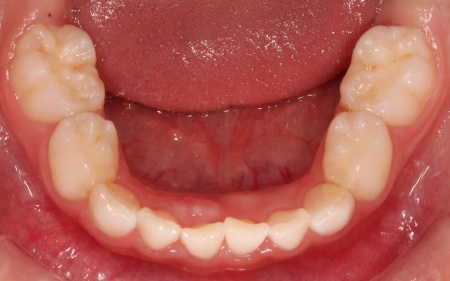

治療前

診断結果 拝見したところ、乳歯が隙間なく密集して生えている状態でした。

通常、乳歯の時期には歯と歯の間に発育空隙(はついくくうげき)と呼ばれる自然な隙間や、犬歯の前後に霊長空隙(れいちょうくうげき)と呼ばれる特徴的な隙間があります。

この隙間は、将来永久歯が生えるために必要なスペースを確保するためのものです。

しかし、患者様はこれらの重要な隙間がほとんど見られませんでした。

今のままでは、今後永久歯が適切な位置に並ぶためのスペースが不足すると考えられます。